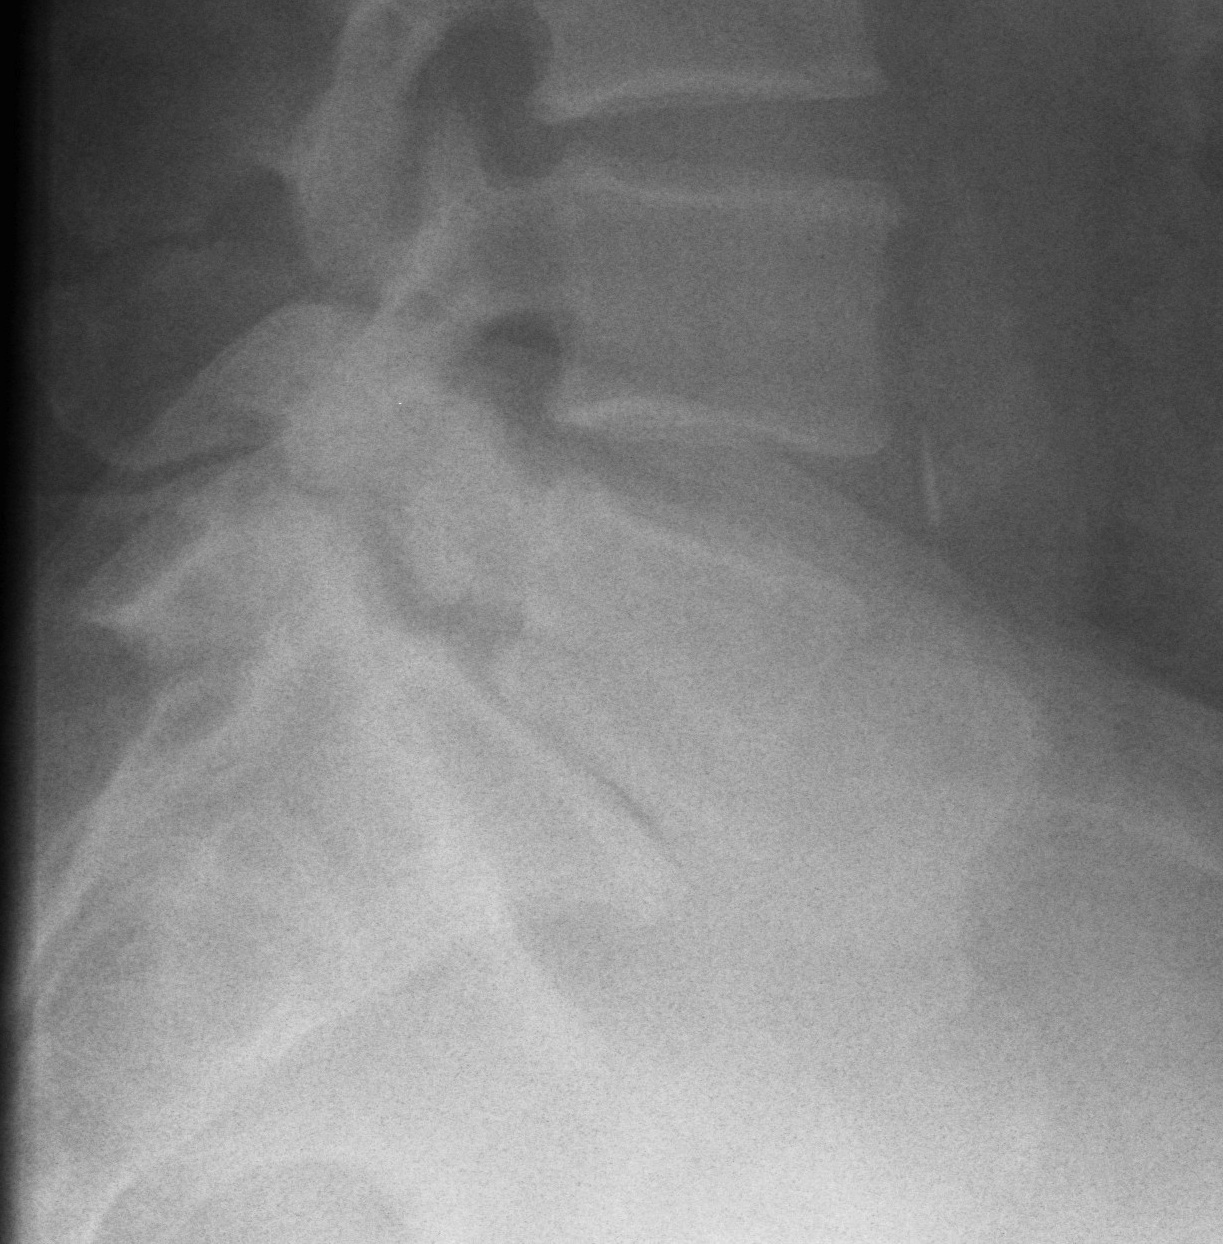

Standing AP and Lateral X-ray

Findings

May miss subtle listhesis on supine XR

- spondylosis

- Meyerding classification

- slip angle

- sacral inclination

Chronic Changes

Seen in older presentation

- anterior sacral erosion

- domed sacrum

- L5 Trapezoidal

- L5/S1 disc degeneration